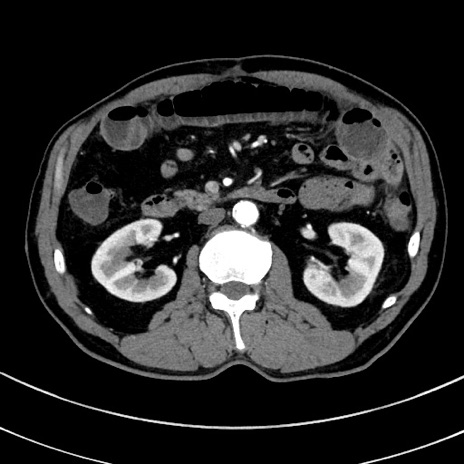

冠状断像

【症例】 60歳代男性

【主訴】 黒色吐物

【現病歴】 4日前から嘔気自覚、2日前の朝食後にも嘔気あり、自分で手で嘔吐反射起こし嘔吐したところ血が混ざっていたため受診。

【既往歴】 5年前汎発性腹膜炎を伴う急性虫垂炎で手術、高血圧、前立腺肥大症、高脂血症

【身体所見】 腹部正中に手術癩痕あり 腹部平坦・軟圧痛なし膨満感あり

【データ】WBC 8400、CRP 4.54